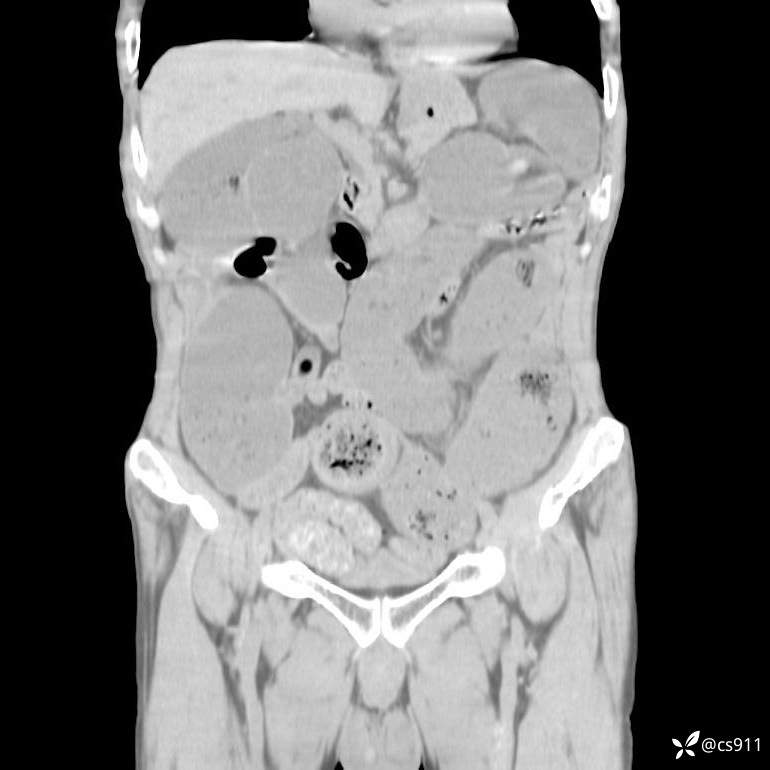

急腹症之急诊CT,原因?答案公布

男,77岁,腹痛、腹胀伴恶心呕吐1天。呕吐胃内容物,非喷射性呕吐,有咖啡色样胃内容物,诉有胃穿孔病史。查体:全腹平,下腹部压痛,全腹无反跳痛,叩诊呈浊音,移动性浊音阴性,肠鸣音减弱,1-2次/分。肛检:直肠未扪及明显肿物,可触及大量粪块。

T 36.6℃ P 80次/分 R 26次/分 BP 100/60mmHg

白细胞(WBC) H 14.55 10e9/L 4-10

中性粒细胞百分率(NEUT%) H 85.7 % 40-75

血淀粉酶(AMY) HH 1859 U/L 35-135

癌胚抗原(CEA) H 27.44 ng/ml 0-5

呕吐物 潜血试验 * 阳性 阴性

患者轮椅入室检查神志清楚, 能配合摆位和呼吸